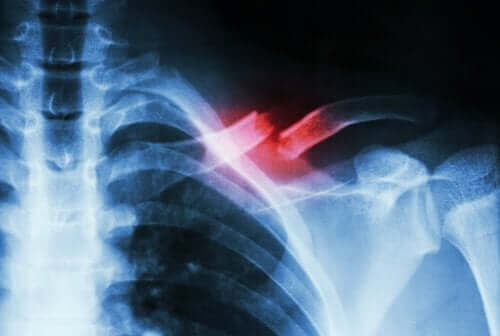

Не забувайте, що діагностувати стресовий перелом досить складно. Лише з допомогою кваліфікованого спеціаліста та низки додаткових тестів можна відрізнити цю травму від інших серйозних ускладнень. На жаль, пошкодження є настільки маленьким, що зазвичай його навіть не можна розгледіти на рентгенівських знімках.

При стресовому переломі кістка надламується або розколюється. Як ми вже згадували раніше, найчастіше провокують цю травму повторювані мікротравми або перевантаження організму. Варто зауважити, що під час фізичного навантаження людина з цією травмою може відчувати сильний біль, який зазвичай зникає одразу після завершення тренування.